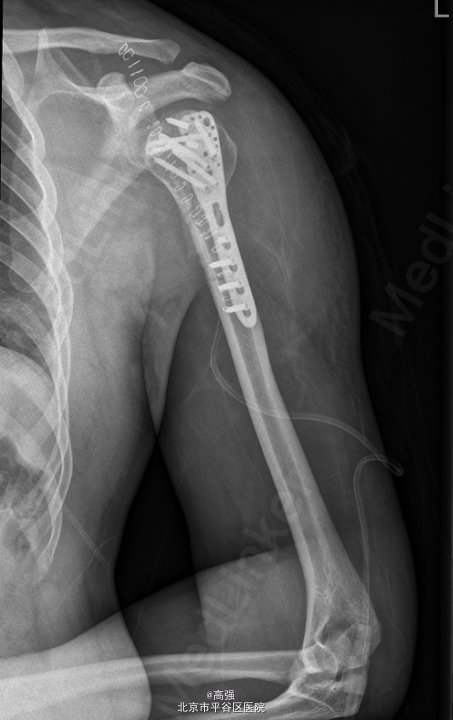

初步诊断: 左肱骨近端粉碎性骨折 行左肱骨骨折切复内固定术